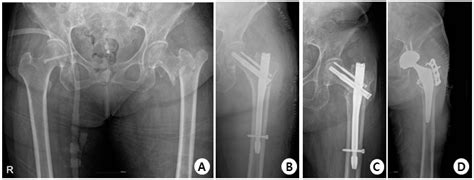

The Trochanteric Fixation Nail (TFN) is a type of intramedullary nail used primarily for the treatment of intertrochanteric and subtrochanteric fractures of the femur. These fractures are common in elderly patients, often resulting from falls or other traumatic events. The TFN is designed to provide stable fixation, allowing for early mobilization and rehabilitation.

The surgical procedure for inserting a Trochanteric Fixation Nail involves several key steps:

1. Preoperative Planning: Detailed imaging, such as X-rays or CT scans, is used to assess the fracture pattern and plan the surgical approach.

2. Patient Positioning: The patient is typically positioned supine on a fracture table, allowing for fluoroscopic imaging during the procedure.

3. Incision and Approach: A small incision is made over the greater trochanter, and the fracture site is exposed.

4. Nail Insertion: The TFN is inserted into the medullary canal of the femur, crossing the fracture site.

5. Proximal Locking: Proximal locking screws are placed to secure the nail in the femoral head and neck.

6. Distal Locking: Distal locking screws are inserted to stabilize the nail in the shaft of the femur.

7. Closure: The incision is closed in layers, and a dressing is applied.